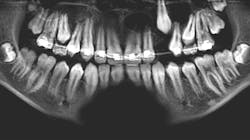

A 14-year-old female presented to her general dentist complaining of pain in the right posterior mandible and mobility of tooth no. 31. Her medical history was otherwise unremarkable. A panoramic radiograph revealed a large, multilocular radiolucent lesion within the entire ramus and posterior body of the right mandible. Tooth no. 32 was within the lesion. Cortical expansion in the area of the lesion was notable. All adjacent teeth were vital. A panoramic radiograph taken at the completion of orthodontic treatment 18 months previously showed no evidence of the lesion.

The keratocystic odontogenic tumor of the right posterior mandible was treated in the classical fashion for this entity by aggressive enucleation and curettage. Preoperatively, a 3D stereolithographic model of the mandible was obtained (figures 1-5), with the extent of the lesion defined, primarily to facilitate ease of adaptation should it be determined intraoperatively that a reconstruction plate would be required to reinforce the compromised mandible.

The lesion was removed via an intraoral approach and curetted from the cavity with the cyst intact. A margin of the cavity was removed using a rotary bur, and the cavity was treated with Carnoy’s solution following removal. Tooth no. 31 was noted to be intimately associated with the cyst and was removed. In four months since the surgery, repeat CBCT has demonstrated excellent bone formation within the cavity and no evidence of recurrence (figure 6).